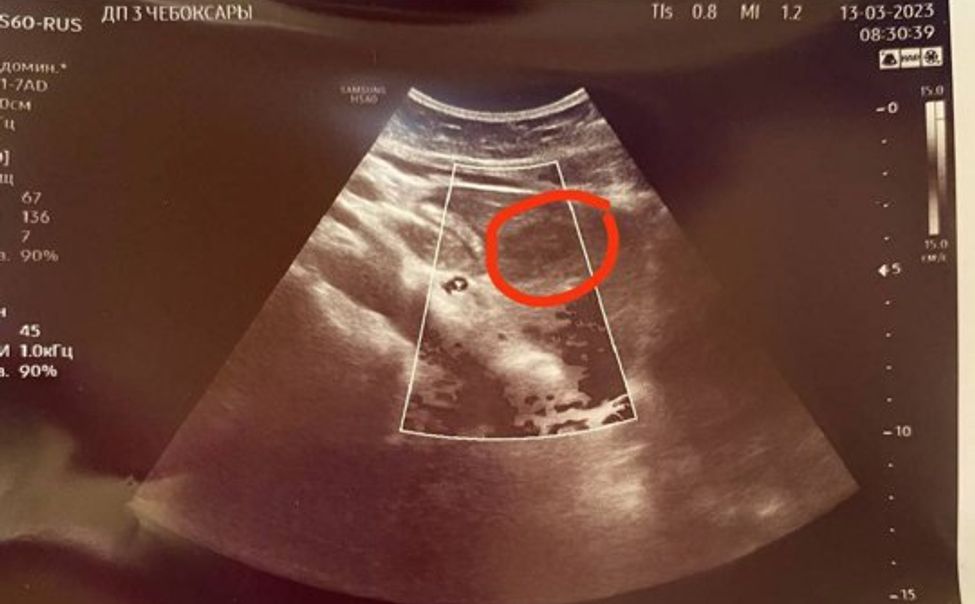

В Чебоксарах при диспансеризации у девочки-подростка обнаружили образование в печени

Во время диспансеризации врачи ультразвуковой диагностики Городской детской клинической больницы обнаружили у 14-летней пациентки образование в печени.

В Чебоксарах в ходе диспансеризации у подростка обнаружили 3-сантиметровую кисту почки

При прохождении диспансеризации у 15-летней девочки во время ультразвукового исследования органов брюшной полости врачи обнаружили кисту почки диаметром 3 см. У подростка на момент осмотра не было никаких жалоб.